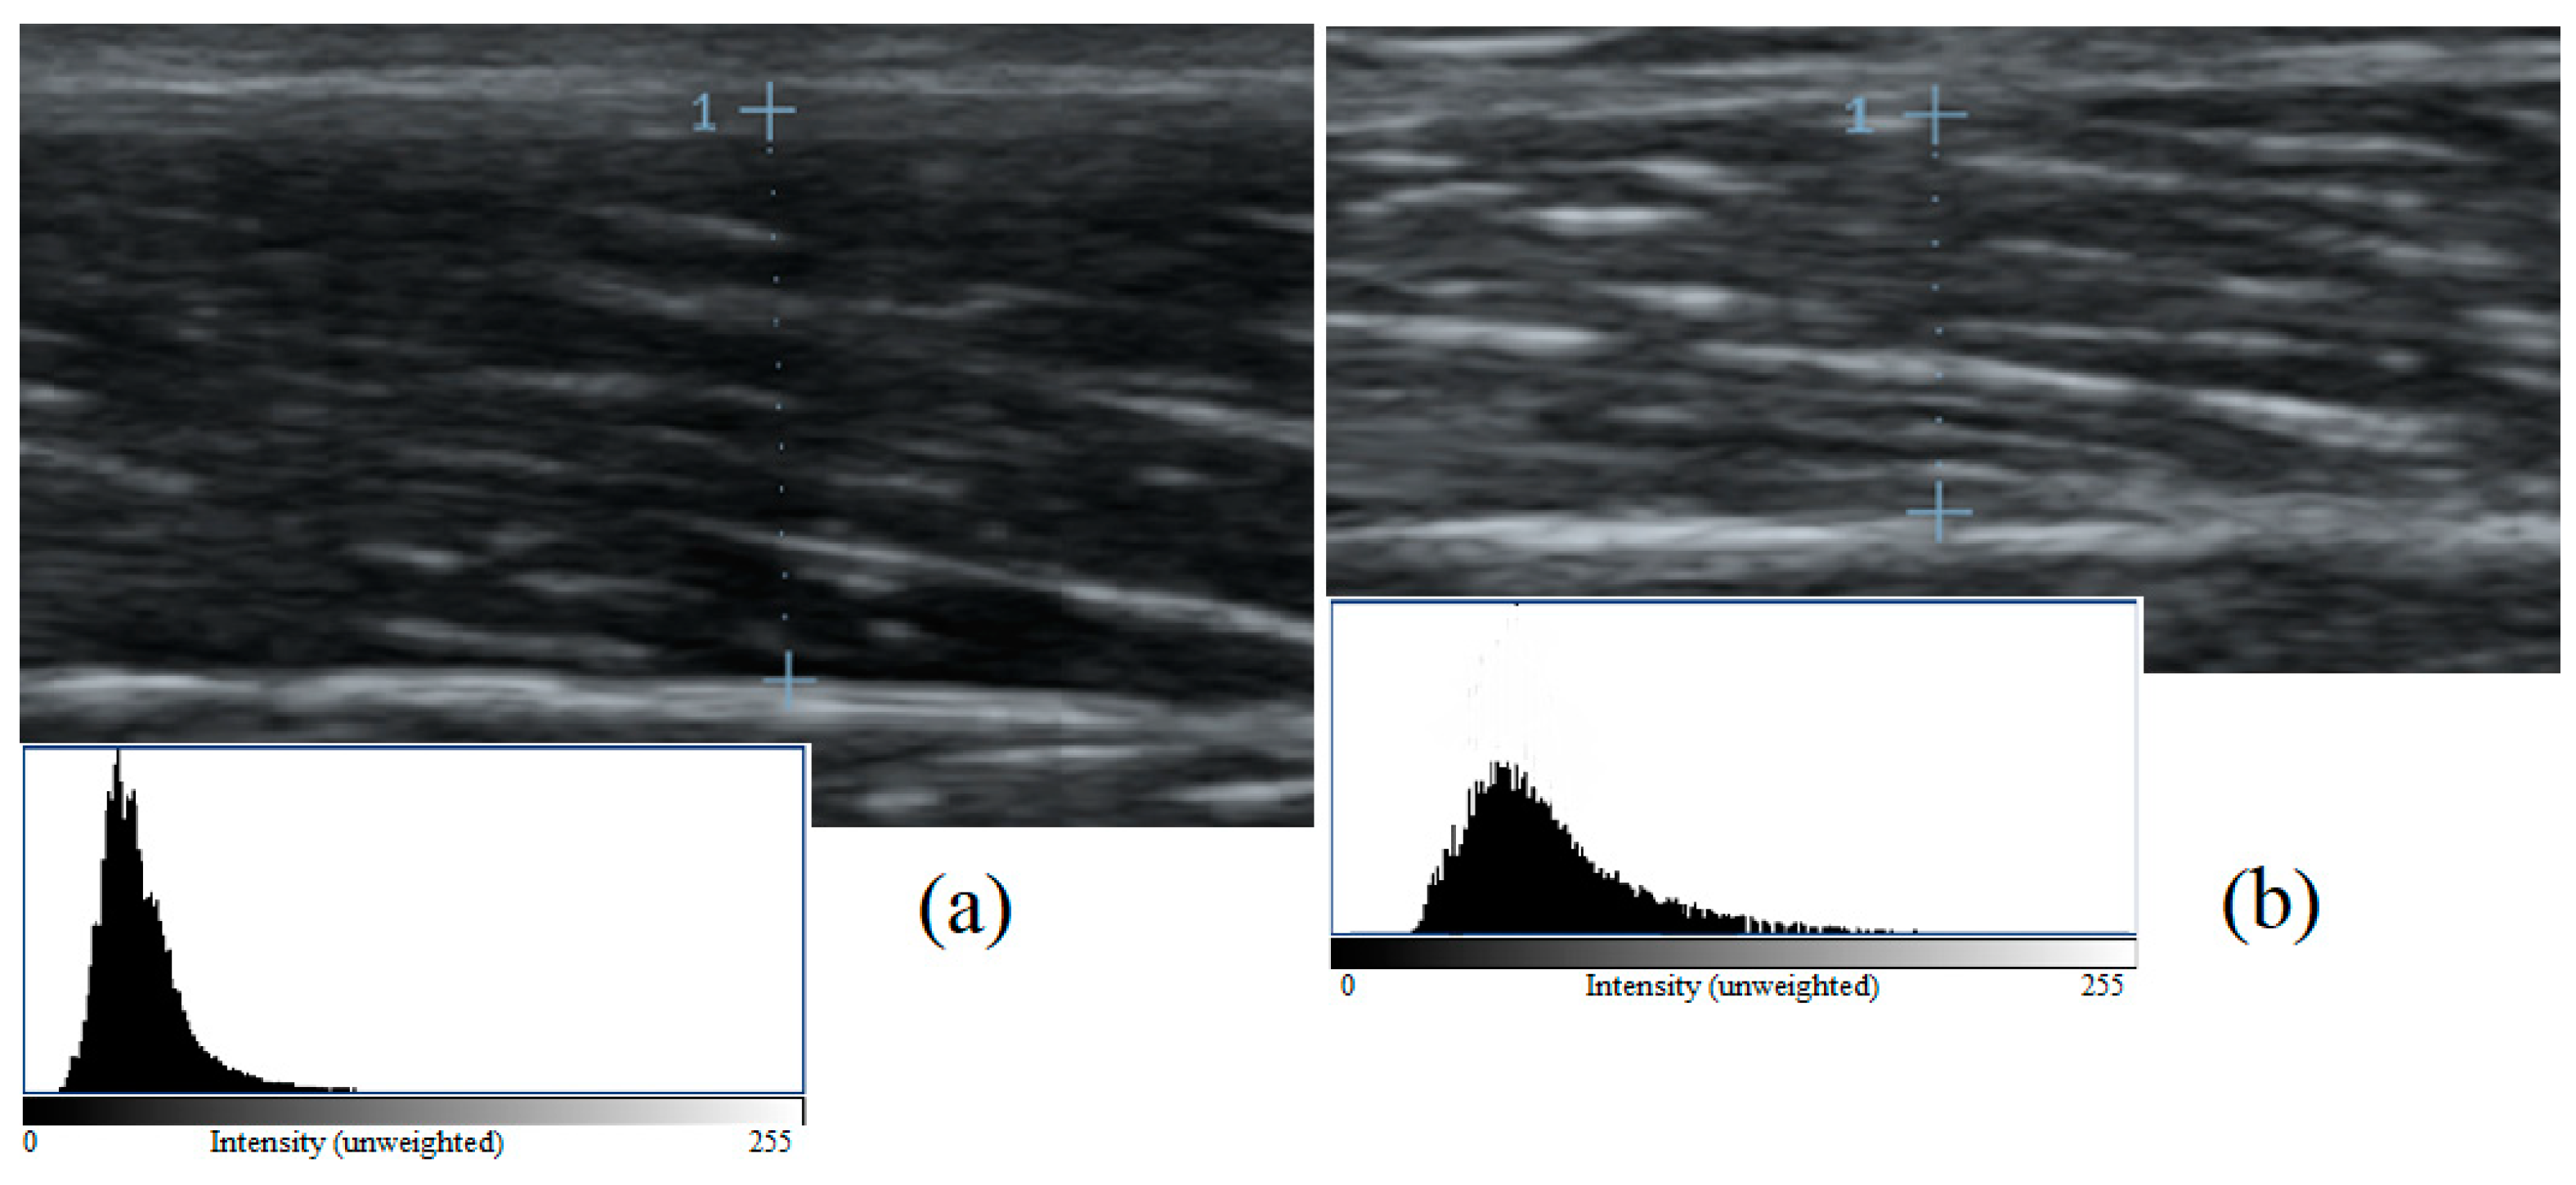

2.3. Body Composition and Muscle Architecture Assessments

| VLEI (a.u.) | 41.22 ± 6.64 * | 52.01 ± 7.89 | <0.001; 0.361, −15.575 |

| VLcEI (a.u.) | 52.64 ± 8.8 * | 77.35 ± 13.71 | ≤0.001; 0.370; 18.008, 33.172 |